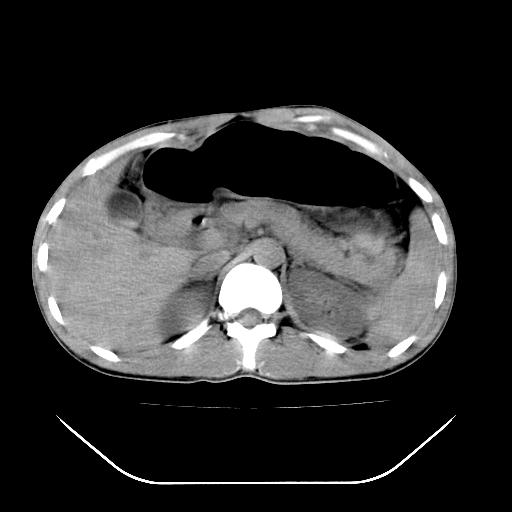

除了1:左肾挫裂伤并肾周血肿;

2:少量腹水

第二次ct检查后:临床医生腹水穿刺后考虑肠系膜动脉破裂,后实行剖腹探查:于空肠距离十二指肠90cm处发现肠管破裂,破裂口较小;修补后关腹。

谢谢各位老师精彩的讨论

顺便请各位老师认真看看7号片

各位老师觉得胆囊是不是有点积血。我在原始片看胆囊密度不均,似有小液平面

再有就是支持楼主,胆囊7日片比5日片不仅增大许多,靠后下更见液液分层,应该是有积血。